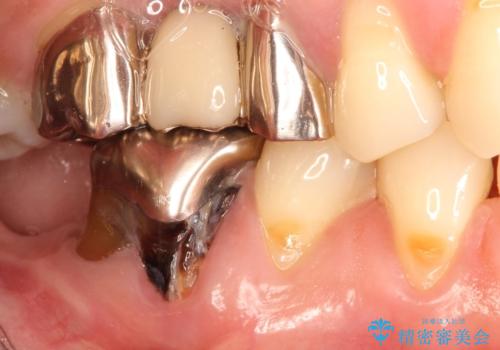

奥歯が痛い。抜歯~奥歯のインプラント

- 奥歯が破折していたため、抜歯を行ったあとインプラントを埋入して咬合回復を行っております。